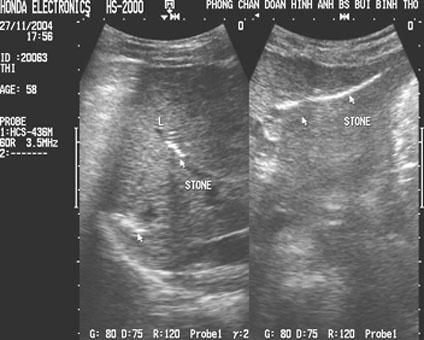

Aspect hyperechoriche

avec de zone de faible acoustique posterieure d'une calcul du

canal hepatique ( fleche blanche ) . Voie

biliaire en amont est tres dilate . Image

echographique per cutanee en coupe a longitudinal de

voie biliare principale |

Image echographique d'une

calcul de voie biliaire principale avec image du

calcule et de canal choledocque en dilate ;

20% de calcul choledociennes est hyperdensite (

hyperechogene ) .

Coupe longitudinal du canal |